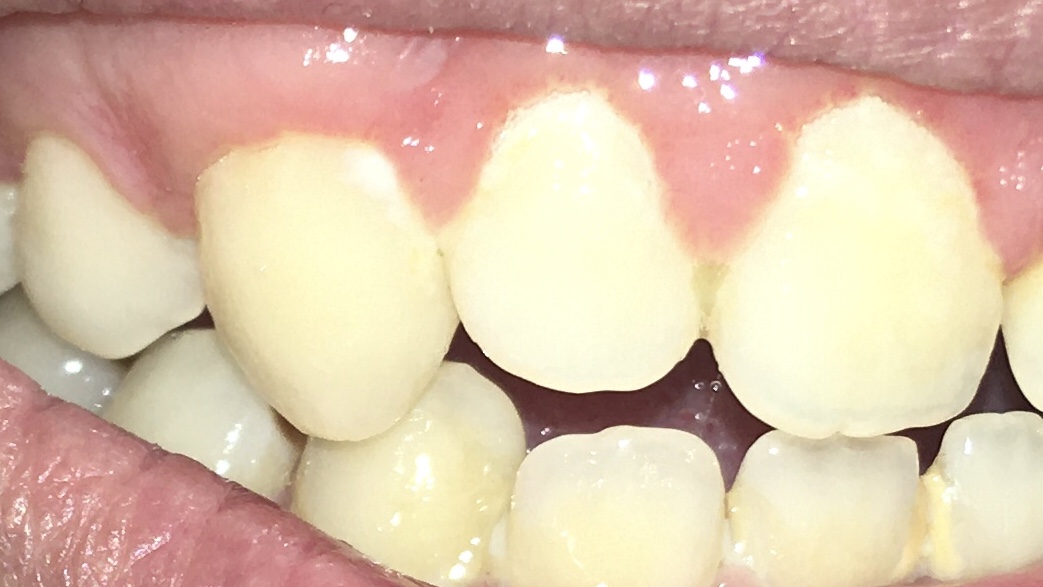

Опустились дёсны в нескольких местах, обнажились шейки зубов. Чувствительные, болят от прикосновений, могут реагировать на холодное, горячее, сладкое.

Ситуация как примерно на пик2.